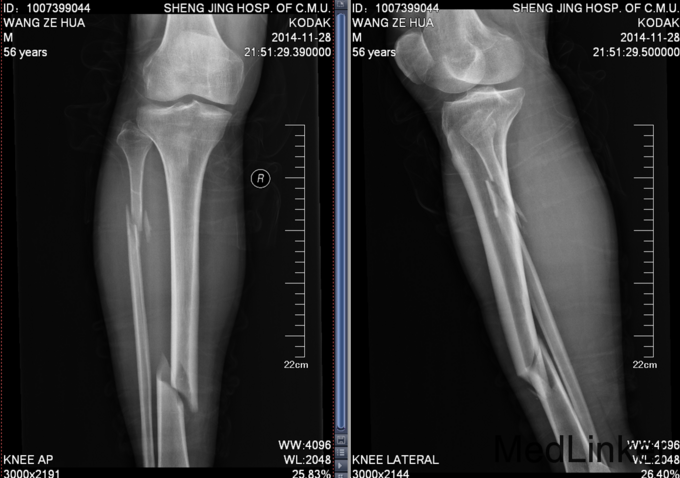

患者2014年11月28日晚上20时自己走路不慎掉入沟中,伤及右小腿,伤后自觉右小腿疼痛明显,肿胀,畸形,遂急诊来中国医科大学盛京医院急诊外科就诊,行右胫腓骨正侧位,提示右胫腓骨骨折,患者为求进一步治疗来我科就诊,急诊以“右胫腓骨骨折”为诊断收入院

患者平车入病房,被迫卧位。有小腿活动受限,肿胀明显、,压痛(+),叩击痛(+),,骨盆分离试验(-),挤压试验(-)右下肢皮肤感觉略麻木,足背动脉可扪及搏动,末梢血运可,足趾可活动。